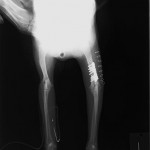

上腕骨骨折 柴犬 体重7.4Kg

手術後

プレート・スクリューによる整復を行いました。